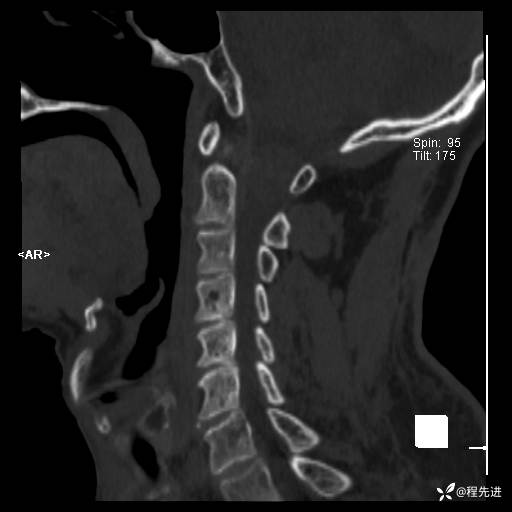

CT平扫: